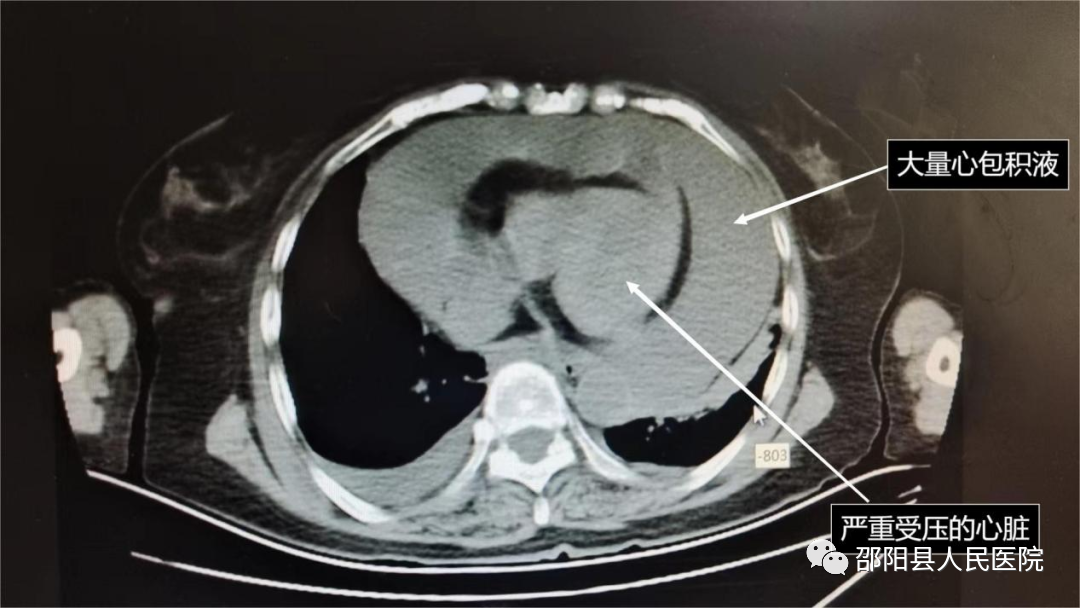

考虑该患者病情危重,心胸外科主任蒋绍军立即组织全科讨论。回顾病史,患者诊断肺癌6月,靶向药物治疗中,因出现胸痛再次入院,结合目前相关资料,考虑肿瘤所致的心包积液,经过治疗,大量心包积液未减少,目前已经出现心包填塞的症状。心脏彩超提示心包腔内大量液性暗区,心尖部深42mm,心脏活动明显受限;胸部CT也提示大量心包积液,心脏形态异常,功能受限。患者病情十分危重,随时可能出现生命危险,需要紧急手术进行心包开窗,解除心脏的压迫。因患者年龄大,既往有高血压病、冠状动脉粥样硬化性心脏病,在心包开窗时,还可能遭遇剧烈的血流动力学变化,手术过程中随时可能出现恶性心律失常、心脏骤停、心脏破裂等严重并发症,手术风险大,但手术时间却不容推迟。蒋绍军主任与湖南省儿童医院派驻医生立即进行商讨,并紧急联合麻醉手术科,制定了详细的手术计划,再向患者家属进行沟通并取得家属的同意,立即安排了急诊手术。

上午九时许,患者进入手术室,充分完善相关准备后开始手术。在湖南省儿童医院派驻医生的辅助下,以蒋绍军主任为首的胸外科医疗团队迅速建立胸腔镜辅助切口,通过胸腔镜观察到患者的心包明显增大,避开膈神经后,在心包裸区切开一个小口,立即见暗红色血性心包积液喷出,说明心包内压力非常大,心脏受压严重,颜色性质也符合肿瘤性心包积液的改变;予以控制切口缓慢释放心包积液,同时药物维持血流动力学平稳,最终引流出的心包积液总量达到了1100ml,幸好手术及时,不然后果不堪设想;最后在心包裸区剪除部分心包进行心包开窗,放置心包引流管及胸腔引流管,逐层关胸,手术顺利,术中患者生命体征维持稳定,术后快速苏醒后,安返病房,目前康复治疗中。